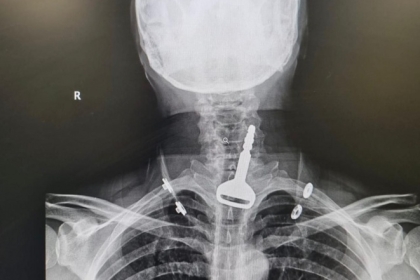

جراح سعودي ينقذ حياة أربعيني ابتلع مفتاح سيارته